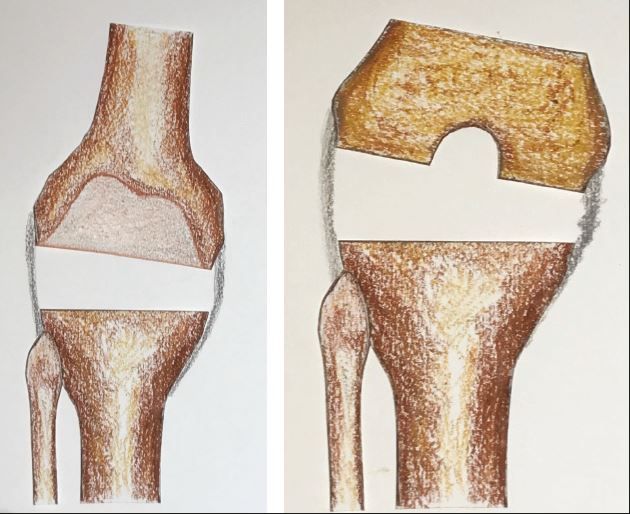

Scenario 2:

- Extension gap tight medially

- Flexion gap symmetrical

- Implies that collaterals balanced

- Therefore either contracture is posteromedial or it implies that there is EAD in the femur. If the former is the case, it should correct with posteromedial capsular release2

- If it doesn’t correct, Sliding Medial Condylar Osteotomy4 may rarely be required.

In the presence of femoral EAD, a persistent trapezoidal extension gap is addressed by distally sliding the medial condyle by the amount required to equalise medial and lateral gaps in extension. As the condyle is not slid anteriorly or posteriorly, it does not affect the flexion gap symmetry.